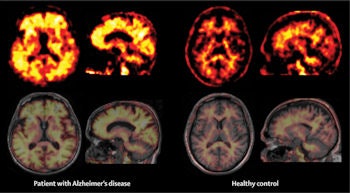

Representative amyloid PET images of a patient with Alzheimer's disease and a healthy control obtained with the F-18 labelled tracer Florbetaben. Nonspecific white matter binding, as seen in the healthy control, spreads to the neocortical gray matter in the patient with Alzheimer's disease as a sign of cortical amyloid β load. Image courtesy of the Lancet Neurology.